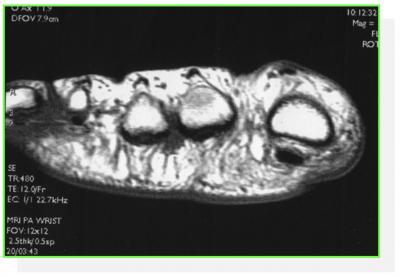

LE NEVROME DE MORTON

Les microtrautismes au sein du canal métatarsien provoque une irritation du nerf interdigital plantaire appelé Névrome de Morton

ECHOGRAPHIE

IRM